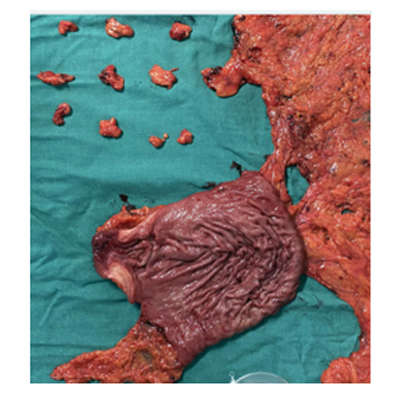

CANCER STOMACH

SURGERY FOR GALL BLADDER CANCER

SURGERY FOR BILE DUCT CANCER

SURGERY FOR LIVER CANCER

SURGERY FOR COLON CANCER